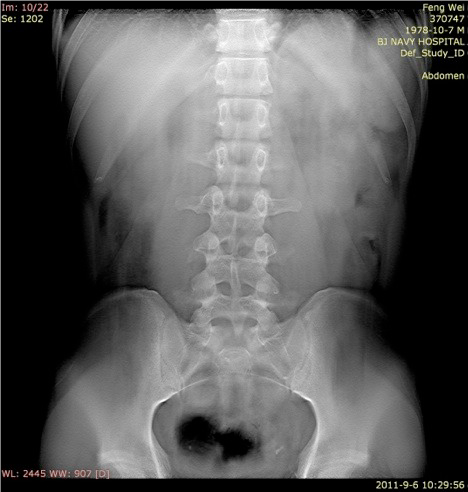

断层容积图片:

影像描述: X线平片:立位X线腹部平片可疑盆腔内(左侧)点状高密度影,但由于肠道气体影响,双肾影无法显示(患者不愿意接受清洁灌肠)。 断层容积图像:去除了肠道气体的影响,清晰显示盆腔内(左侧)点状高密度影,同时显示左肾中部多发点状高密度影。 断层容积诊断: 左侧输尿管盆内段结石,左肾多发结石。 病例点评: 清洁灌肠,是怀疑泌尿系结石时X线腹部平片检查前的常规准备,许多患者不愿意接受这种暴露,接触敏感部位的检查,清洁灌肠也会给患者带来很大的痛苦。断层容积成像完全不需要清洁灌肠准备。肾结石,输尿管下端结石同时显示,说明断层容积成像能大范围清晰显示病变。